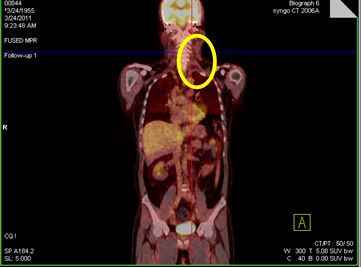

v Bệnh nhân được đánh giá đáp ứng hoàn toàn, tiếp tục theo dõi và khám định kỳ. Hiện tại sau điều trị 6 năm bệnh nhân ổn định. Hình ảnh PET/CT không thấy tăng hấp thu FDG bất thường tại cơ quan bộ phận nào khác của cơ thể.

Hình 3: Hình ảnh PET/CT sau điều trị 6 năm không thấy tăng hấp thu FDG bất thường tại cơ quan bộ phận nào khác của cơ thể.